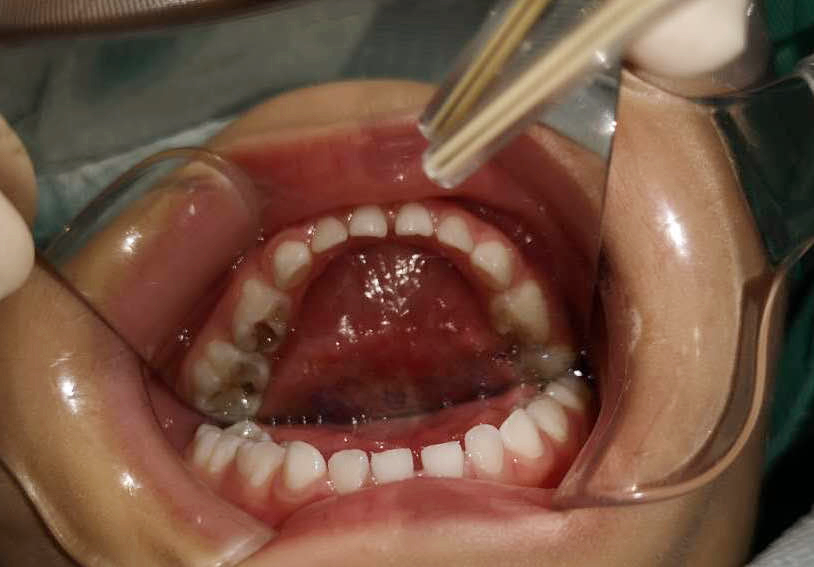

調(diào)節(jié)前

齲齒充填、根管調(diào)節(jié)、窩溝封閉......西海岸新區(qū)中心醫(yī)院的兒童口腔醫(yī)生丁彬主治醫(yī)師和申家麗住院醫(yī)師有條不紊地進(jìn)行著操作,劉亞芳醫(yī)師、李雪飛醫(yī)師和高聰醫(yī)師在旁邊配合著操作,一切井然有序,只有儀器發(fā)出“嘀、嘀”的聲音,提醒著時(shí)間的流逝。

丁彬醫(yī)師和申家麗醫(yī)師正在為小患者進(jìn)行全麻下牙齒調(diào)節(jié)

兩個(gè)多小時(shí)后,這一多達(dá)8顆患牙的復(fù)雜調(diào)節(jié)順利完成。在這期間,鑫鑫的心率和血壓一直被密切監(jiān)測(cè)著,一切都很正常。